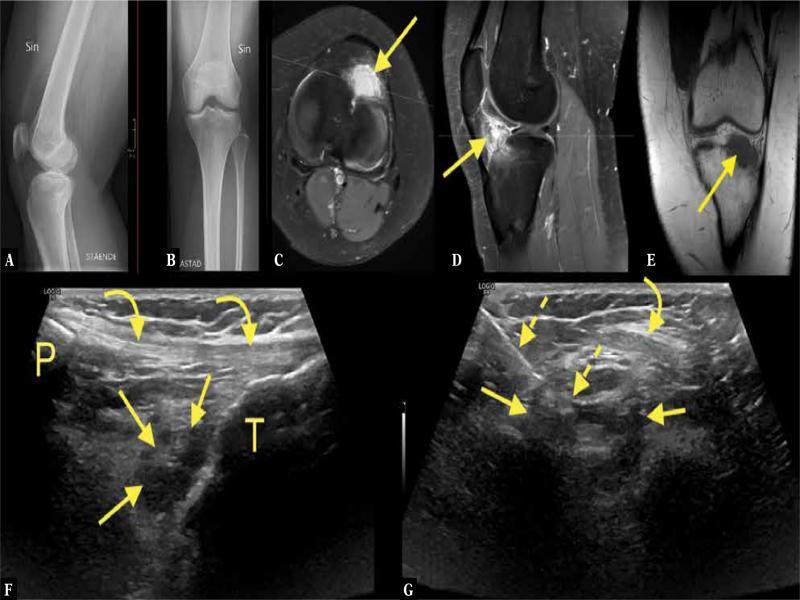

Fig. 5.

A 22-year-old patient presenting with knee pain. Radiography ( A, B ) showed no abnormality. The patient was referred for MRI, which revealed an uncalcified solid contrast-enhancing lesion ( C–E ; straight arrow – lesion) in the Hoffa fat pad. Localized nodular synovitis was suspected. Because of pain, the patient was referred for US-CNB ( F, G ; dashed arrow – biopsy needle, curved arrow – patellar tendon, P – patella, T – tibia). The pathological diagnosis was lipoma arborescens